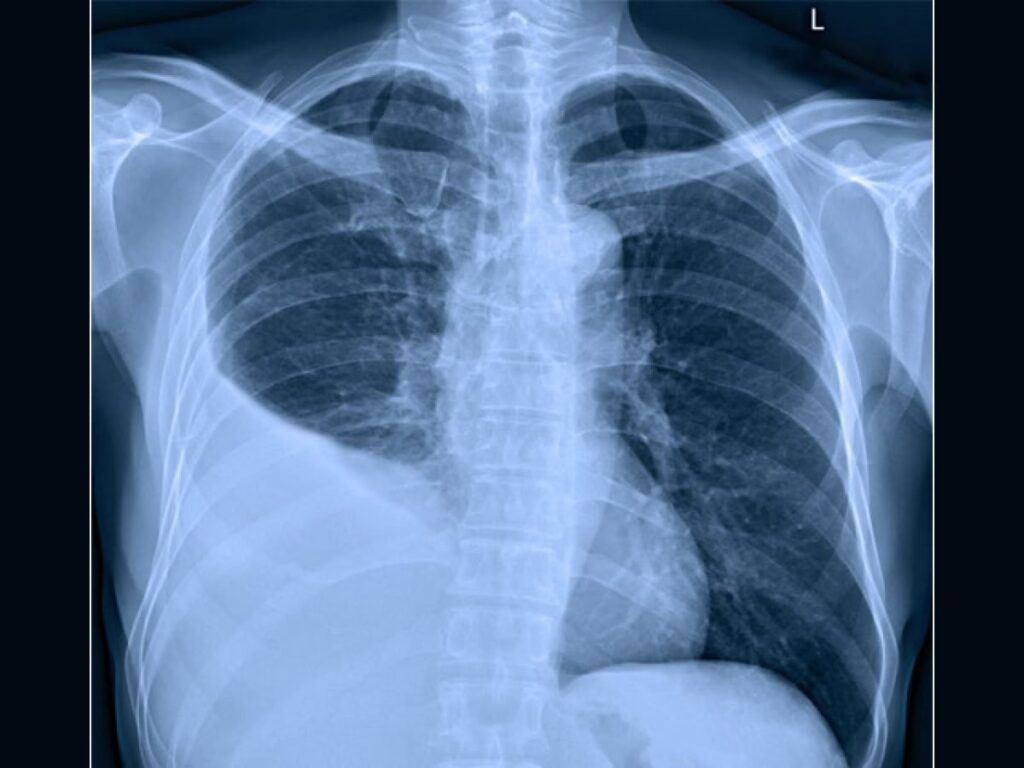

- Røntgen af thorax (brystkassen): Dette er typisk den første undersøgelse. Et røntgenbillede kan vise tegn på lungebetændelse (et infiltrat) og samtidig afsløre tilstedeværelsen af væske i pleurahulen. Et billede taget, mens patienten ligger på siden (lateral dekubitus), kan hjælpe med at vurdere mængden af væske og om den er fritflydende.